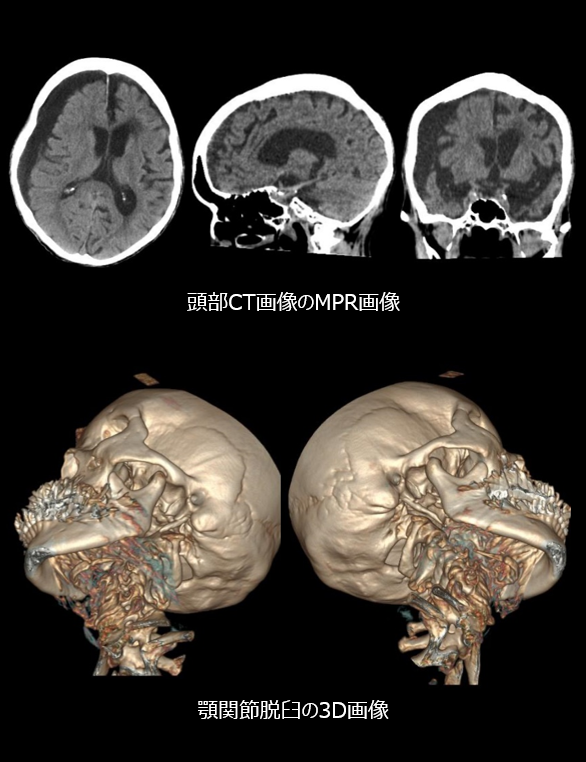

アキシャル断面だけでなく、いわゆるMPR画像(サジタル・コロナル断面)や 3D画質が向上している。

3.非常に使い勝手のよい、MPR・3D作成ソフトウエアにより短時間内での画像処理が可能。

また、上記 2. と 3. により、CT検査のほぼ全例でMPR 画像を作成し、必要に応じて3D画像を作成しています。 作成にかかる時間はかなり短く、他業務に影響を与える ことはありません。

臨床例を1つ紹介します。顎関節脱臼の疑いでCT検査を施行しました。

撮影自体は数秒で終了し、圧倒的な 画像処理スピードで、検査後すぐに3D、MPR画像を作成できました。

作成された3D画像を確認すると、顎関節の 脱臼は容易に観察することができました。

担当医師からは、整復する手法に対するシミュレーションも可能になるし、患者様への説明も容易になったと高評価でした。

cv_man_nari_04.png